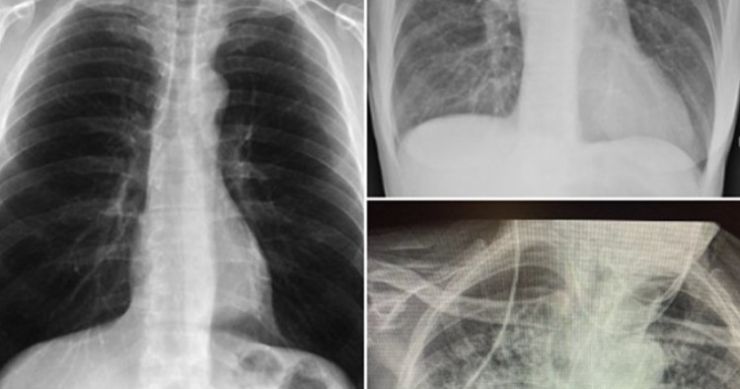

Naime, ona je na svom Twitter profilu podijelila tri rendgenske snimke pluća: jednog zdravog pacijenta, jednog pušača i jednog pacijenta koji je prebolio koronavirus.

Rendgenski snimci

– Ne znam tko ovo treba vidjeti, ali pluća nakon Covida izgledaju gore od bilo koje vrste pluća pušača koju smo ikad vidjeli. I ona se urušavaju. I zgrušavaju. I otežano disanje se zadržava… i dalje … i dalje – napisala je uz rendgenske snimke.

Snimka pluća zdravog pacijenta je bistra jer imaju puno crnog prostora, što ukazuje na to da osoba može udahnuti puno zraka. Gledajući rendgen pluća pušača, primjetna je maglovitost koja ukazuje na ožiljke i začepljenja. Treća slika prikazuje pluća nakon Covida, koja izgledaju gotovo potpuno bijelo, što znači da su pluća ozbiljno oštećena. Nakon što je njezin tvit dobio puno pažnje i hiljade odgovora, doktorica je pozvana da kaže nekoliko riječi u vijestima na CBS-u.